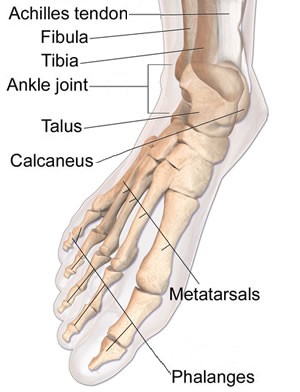

Specific Dislocation/Luxation Cure: Ankle

The ankle is one of the two dislocations mentioned by all the authors under study, the other being the shoulder. As he did with several other luxations, sea surgeon John Woodall only mentions it as something that can easily be repaired with his device the commander.1 All the other authors have more to say on repairing an ankle dislocation. Sea surgeon John Atkins advises that because the ankle joint is so "fast bound with Membranes, Ligaments, and Tendons, makes it very difficult of Luxation."2 While English surgeon Richard Wiseman agrees with his assessment in theory, he explains that the ankle "would not easily be dislocated, did not so great a weight lie thereupon."3

Image: James Hielman - Forward Dislocation of the Ankle

The ankle can be dislocated inward, outward, forward and backward. Everyone attempts to explain the symptoms of each type of ankle dislocation by its appearance, but most of them are more confusing than helpful. Sea surgeon James Handley gives the most cogent explanation:

If it be Dislocated inward, the sole of the Foot turns outward, and if dislocated outward, it turns the contrary Way: if forward, the broad Tendon of the Heel... is, torte [taut] and hard, and the Foot is less [shorter than normal]: if the Dislocation be backwards, the Heel is almost hid, the sole of the Foot seems bigger, and the Foot longer.4

Atkins adds that the more perfect or complete the luxation is the more likely it will suffer "insupportable Pain, a long and tedious Weakness, and sometimes irrecoverable Lameness."5 However, he also warns that such symptoms are present in ankle sprains, but since "it is not easy to perceive any small Distortion of the Bone through a large Tumor, or a peculiar Conformity; I say, in regard to this, it is not implolitick to recommend Extension at all times"6.

French surgeon Ambroise Paré says that ankle dislocations do not "happen without much violence"7. Atkins, on the other hand, notes that partial ankle dislocations can be caused by 'slight accidents' "such as slipping on an uneven Surface, sudden Stumbles and Falls"8. Although he doesn't say so, it is likely that Paré is talking about complete dislocations while Atkins specifically says he is talking about partial dislocations.